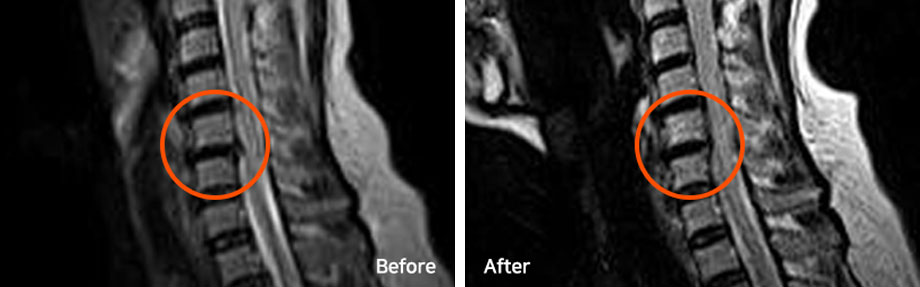

파열된 목디스크는 치료를 잘 받으면서 충분한 휴식을 취하면 우리 몸으로 흡수되어 없어지는 경우가 많고, 파열이 심할수록 오히려 더 잘 흡수되기도 합니다. 단, 디스크로 다시 재흡수되는 것이 아니라 우리 몸의 대식세포 등이 튀어나온 디스크를 이물질로 인식해 녹여서 몸속으로 흡수되어 없어지는 것입니다. 오른쪽 MRI 사진은 치료 6개월 후 촬영된 모습으로, 파열된 디스크가 깨끗하게 흡수된 것을 확인하실 수 있습니다.